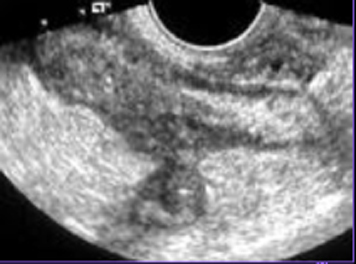

| Aspect a jejunisation de

ileon dans maladie coeliaque . Signe de " grele

inverse" Image TDM en coupe axiale a

travers de la region pelvienne |

Adenopathie

mesentrique est peut presente avec image de

perdre etendue de villosite de l'intestin ( fleche jaune ) . |